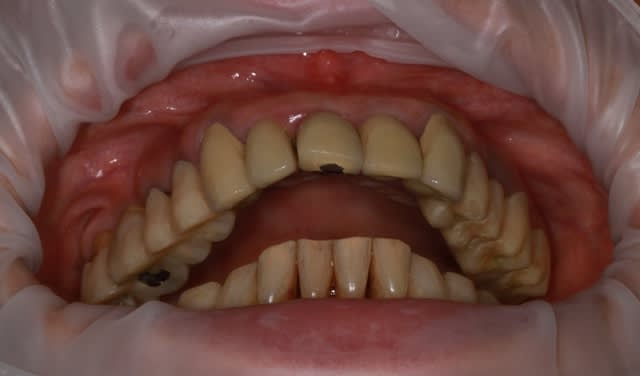

dépose des ceramo métal antérieur, ouf le précédent n'a pas mis d'IC, j'ai plus de marge de manœuvre.

Prochaine étape réalisation d'un provisoire résine "complet" pour le max.sup., mais il me faut paralléliser tous les moignons.

j'en suis à la 4eme séance détartrage surface...et ça commence à être propre et sain.

ça commence à sentir bon, dans un premier temps, les provisoires sont en place sans collage (ça marche aussi sur les dents naturelles,pas que sur les implants) pour valider la partie mécanique et permettre aux différents moignons de se positionner bien parallèle, dommage qu'il n'existe pas de "guides" pour ça...

prochaine étape collage des provisoires haut et bas, et mise en attente 1 à 2 mois.

et petit travail sur les antérieurs mandibulaires